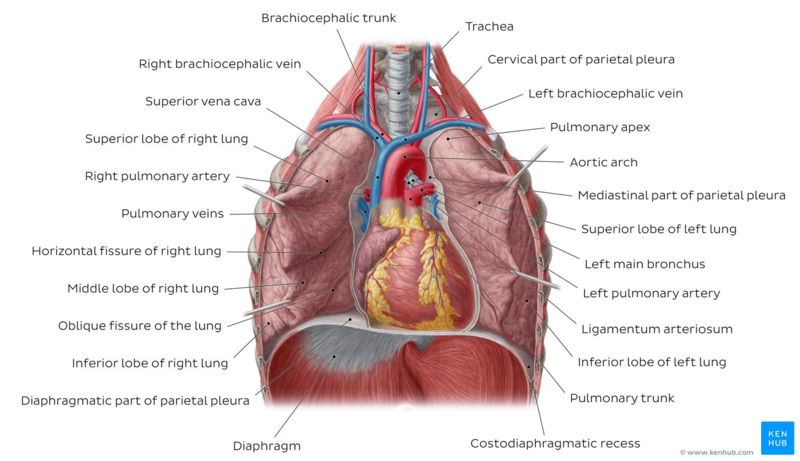

Lungs | Anatomy Of The Thorax | Learn Surgery Online

learnsurgeryonline.com

learnsurgeryonline.com

lung lungs lobes fissures middle inferior divided thorax

lungs thorax posterior anterior pulmonary mhmedical 1901